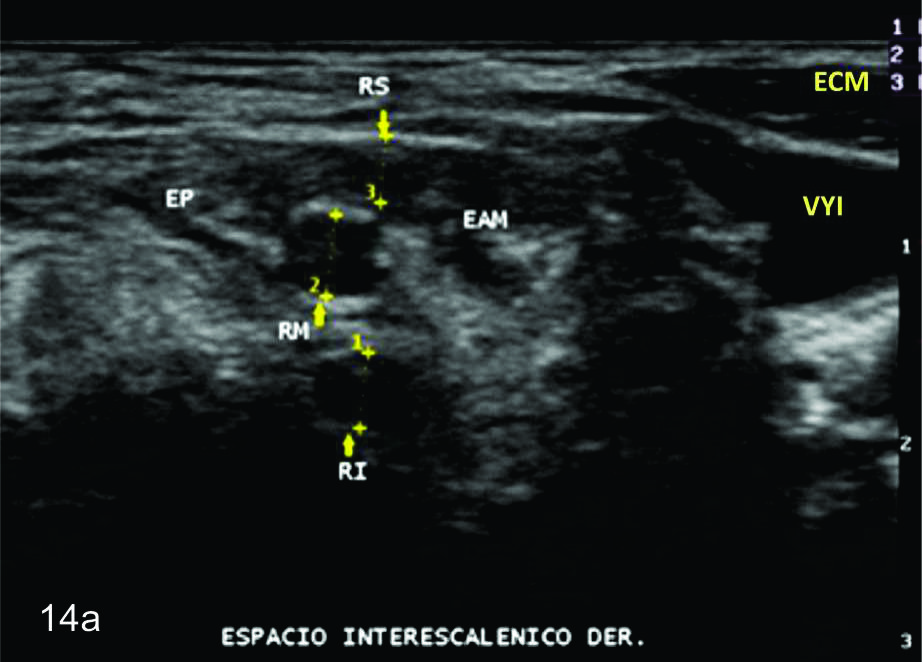

Figura 14 a y b

Lesión traumática del plexo braquial luego de accidente en moto.

A y B- cortes comparativos transversales al plexo braquial al nivel del espacio interescalénico (A-derecho patológico y B-izquierdo sano), se demuestra la asimetría de las estructuras del plexo. RS- tronco superior, RM-tronco medio, RI-tronco inferior, EP- músculo escaleno anterior, EAM-músculos escalenos medio y anterior.

Figura 14 c y d

C y D- cortes comparativos longitudinales sobre el tronco medio del plexo braquial (C- izquierdo sano y D- derecho patológico), se demuestra la asimetría de la raíz media del plexo, la cual se demuestra en un corte longitudinal comparativo (señalada entre calipers amarillos). La flecha blanca en D señala un fragmento óseo desplazado debido a una fractura del proceso transverso vertebral que generaba conflicto con la raíz.

Figura 14 e, f, g y h

EyF-Cortes comparativos a nivel de cara anterior de brazo derecho o afectado (E) y brazo izquierdo o sano (F), en donde se identifica la clara asimetría en el volumen y ecogenicidad de los planos musculares (flechas azules) en relación a cambios por atrofia. H- diáfisis humeral. GyH- Cortes comparativos a nivel de la cara anterior del antebrazo derecho o afectado (H) e izquierdo o sano (G), demuestra hallazgos similares. R- Diafisis radio, C- Diafisis cubito.